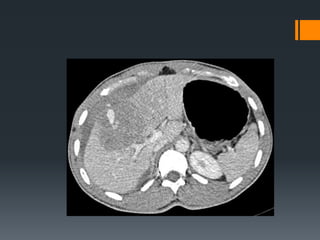

Splenic Trauma